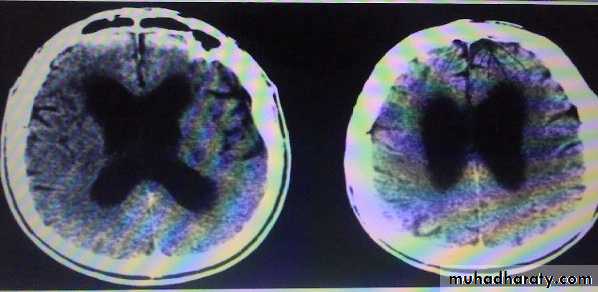

Neuroimaging findings in NPH are those of a communicating (non-obstructive) hydrocephalus with a patent aqueduct of Sylvius. In many cases periventricular edema is present. There is no evidence of cortical or hippocampal atrophy.

The indolent nature of the process results in enlarged lateral ventricles but relatively little increase in CSF pressure.

CT Brain in pt. with NPH